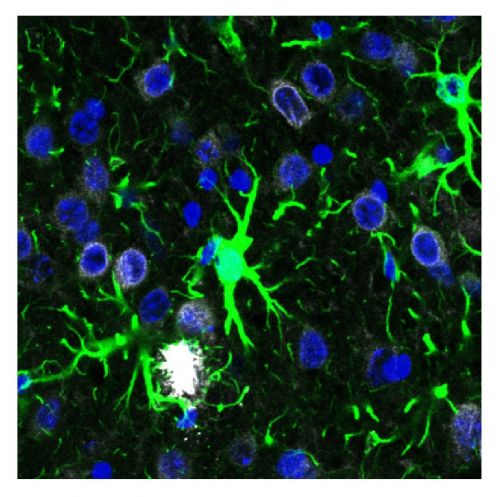

Alterazioni dei segnali intracellulari causano atrofia celebrale e perdita della memoria in caso di morbo di Alzheimer. Un gruppo di ricercatori dell'Istituto di Neuroscienze di CNR di Pisa e del Dipartimento di Scienze Biomediche dell'Università di Padova hanno usato i modelli murini e osservato il funzionamento degli astrociti, cellule che interagiscono dinamicamente coi neuroni. In caso della patologia gli studiosi hanno notato una riduzione nell'attivazione delle unità nella corteccia celebrale e quindi una minore ricezione degli stimoli sensoriali. La diminuzione del segnale è provocata dalla proteina STIM1. Gli esperti hanno quindi indotto la produzione per recuperare la plasticità sinaptica, un metodo che potrebbe essere usato per curare la malattia.